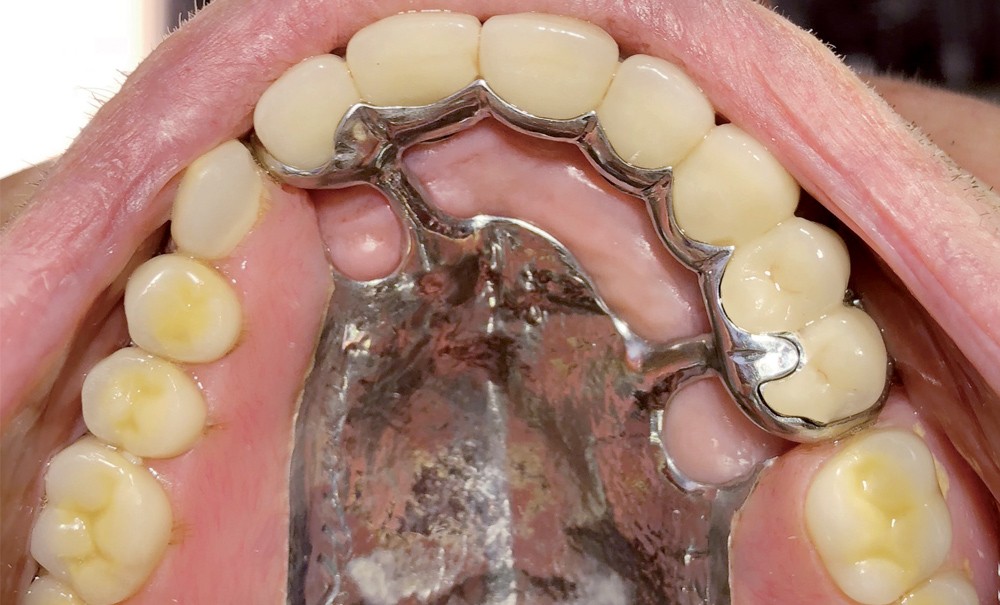

Un patient de 84 ans, en bon état de santé générale, consulte pour la perte de trois couronnes solidarisées métalliques 17, 16 et 15 qui permettaient la rétention d’une PAP à châssis métallique (fig. 1 à 5).